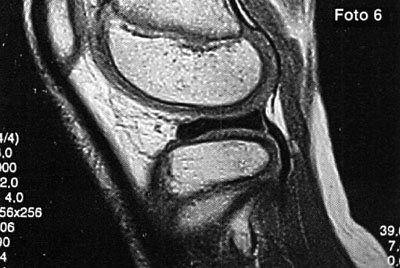

Foto 5: Lesión o.C. visualizada en RMN

Fotos 6 a 10: Lesiones osteocondrales del astrágalo según grado de RMN. (Anderson y cols)

foto 6: Lesión G I

La clasificación a partir de imágenes radiológicas mostró un coeficiente de correlación de Spearman de 0,77 (p=0,001) con respecto a la clasificación realizada a partir de imágenes tomográficas, en tanto que el mismo coeficiente entre las imágenes de TAC y RMN fue de 1 (p < 0,001). Esto implicaría una alta correlación entre la clasificación de TAC y RMN mientras que existiría una menor correlación entre Rx y TAC. En relación a los hallazgos de resonancia magnética, 12 pacientes (29,3 %) presentaron un GI, seis pacientes (14,6 %) presentaron un Gila, siete pacientes (17,1 %) un Glib, trece pacientes (31,7 %) un GIII y tres pacientes (7,31 %) un G IV. (fotos 6 a 10) Dieciocho pacientes (43,9%) fueron tratados en forma conservadora y 23 pacientes(56,1%0) fueron tratados en forma quirúrgica. (Ver tabla 4)